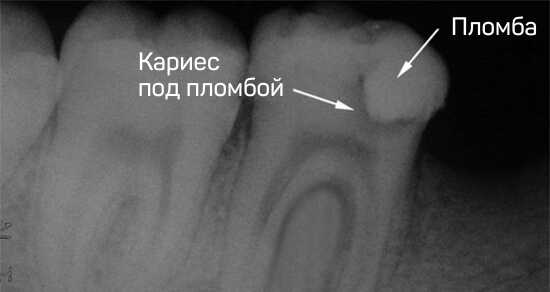

Скрытый или вторичный кариес

Скрытый кариозный процесс незаметен невооруженным глазом. Обнаружить его можно просвечиванием специальным светом или на рентгеновском снимке, где он отображён в виде тёмного пятна.

Вторичный кариес обычно развивается вследствие некачественного эндодонтического лечения каналов зуба. Оставшиеся в них ткани разлагаются, окрашивают зуб изнутри.

Вторичный или скрытый кариес

При развитии скрытого кариеса на поверхности зуба появляется темное матовое пятно, в то время как зуб разрушается изнутри. При этом снаружи пациент не может заметить никаких видимых повреждений. Вторичный кариес возникает вследствие неправильной установки пломбы. В этом случае между пломбой и дентином остается пустое пространство, ткани разрушаются, и дентин меняет цвет.

Скрытый или вторичный кариес. Скрытый кариес выглядит, как темное пятно на эмали или на ней появляется матовый, непрозрачный участок. Зубик при этом разрушается изнутри — снаружи вы «дырку» не увидите. Вторичный кариес часто возникает из-за плохой установки пломбы. Если между пломбой и дентином останется пустота — ткани начнут разрушаться и поменяют цвет.